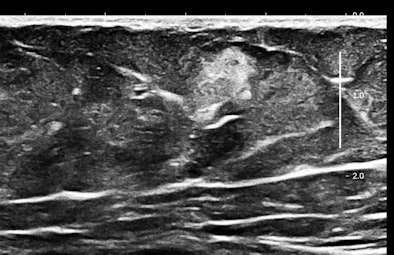

Here are three representative (HD) anterior abdominal wall images at 15 MHz:

Mast cells and mediator-release disorders

These echogenic "nodules" are tumorlike collections and cellular infiltrates of mast cells. The precise diagnosis is systemic mast cell disease. Symptoms are due to mediator release. At one pole is typical carcinoid syndrome involving serotonin and kallekrein, and at the other extreme is anaphylaxis with predominant histaminelike substances. Because of the large number of nodules, there is a significant neuroendocrine burden, similar to the multiple metastases of a malignant carcinoid tumor filling the liver.

Soft, well-demarcated reflective nodules in subcutaneous fat are an Aunt Minnie of a sign. They are not palpable, and I suspect they can only be found by high-frequency ultrasound, which is perfect for outpatient screening applications. There may be a completely unexpected, relatively high prevalence of this finding, and it seems that multiple nodules may predispose several allergic disorders, including conditions such as irritable bowel syndrome (IBS), fibromyalgia, and possibly even exercise-induced asthma or postexertional hypotension and reactive tachycardia.